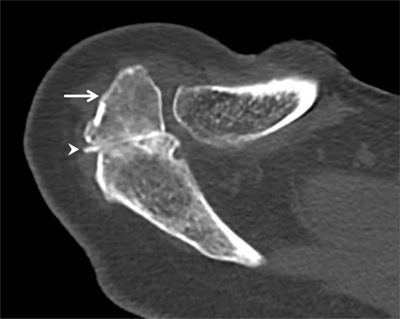

Figure 9

Os acromiale. Axial CT arthrography through the acromioclavicular joint demonstrates an os acromiale (arrow) with synchondrosis (arrowhead). An os acromiale should not be confused with a fracture fragment and the synchondrosis with a pseudarthrosis. In this case, there is a communication between the synchondrosis and the glenohumeral joint (with high-density contrast penetration), which is not normal. Subchondral cystic changes are also seen in the zone of pseudarthrosis.